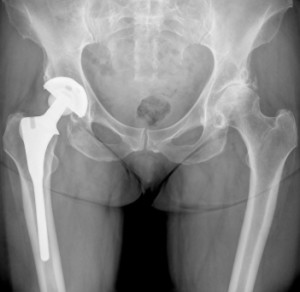

Any type of surgery comes with a risk of complications, with some having higher risks than others. Hip replacement surgery, which involves replacing a worn out, malfunctioning hip with a prosthetic, has become one of the most successful types of medical operations, with a typically low risk of hip replacement complications.

A common design for hip replacement systems is a two-piece acetabular cup — the half-grapefruit-shaped part of the prosthesis that fits into the hip socket. Inside this cup, the surgeon fits a plastic liner, and then places the rounded head of the “femoral” component — also called the “ball” — into the plastic liner.

The ASR was unique in that instead of the standard two-piece design, it was made of a single piece. The design did away with the plastic liner, and instead placed the metal ball of the femoral component directly into the metal acetabular cup — a design that later came to be called a “metal-on-metal” hip implant. This design allowed the ball, or “femoral head” as it’s often called, to be larger so that it would take up all the room inside the cup, in the absence of the liner.